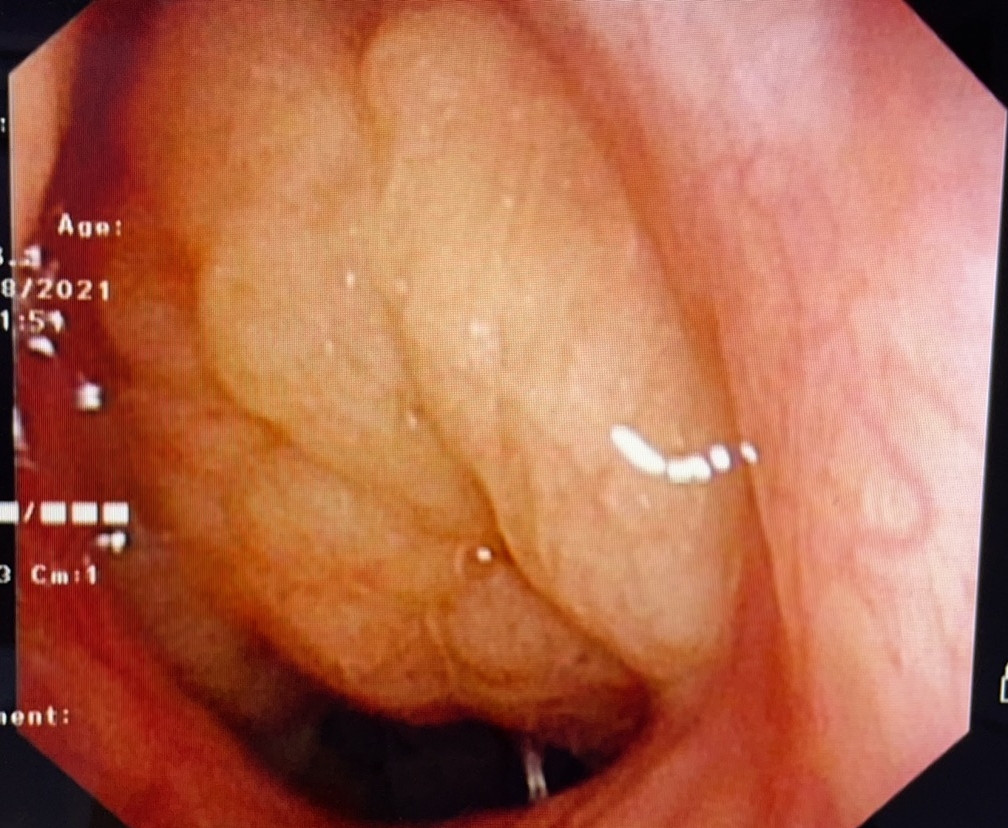

的确能。孩子睡觉时,正常闭着嘴用鼻呼吸时,口腔没有气流通过,舌头很自然就在口腔顶部。长时间张口呼吸,气流冲击硬腭(上牙膛),用力吸气时,面部肌肉收缩,致使面骨发育发生障碍,如颌骨变长、腭骨高拱、牙列不齐、上切牙突出、唇厚、缺乏表情等。这就是腺样体面容。

主要原因是呼吸不通畅。儿童时期易患上呼吸道感染(如急性鼻炎、急性扁桃体炎等)、过敏性疾病(如过敏性鼻炎),若反复发作,腺样体可迅速增生肥大,阻塞后鼻孔、加重鼻阻塞、阻碍鼻腔引流,鼻炎鼻窦炎分泌物又会刺激腺样体,使之继续增生,形成互为因果的恶性循环。肿大的腺样体堵住呼吸要道,孩子只能张嘴呼吸,久而久之就会形成上面所说的“腺样体面容”。